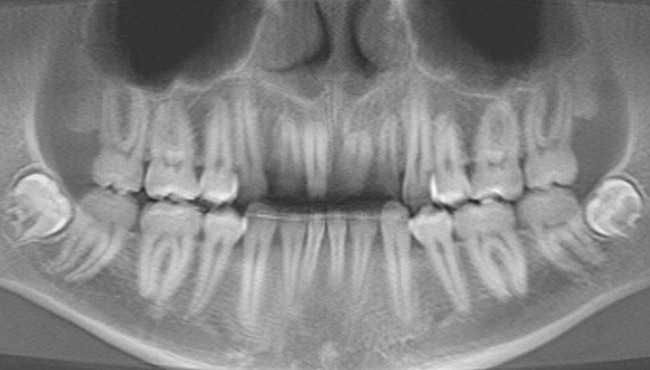

A 24-year-old non-smoking man presented for treatment of a horizontally fractured left central incisor (Figure 21 and Figure 22). The patient requested to have an implant placed to replace the left central incisor as to not have any damage to the adjacent dentition.

Complicating the treatment site was the apically positioned facial height of contour at the left central incisor, and the adjacent left lateral incisor (Figure 21.) Additional sites of recession were present throughout the oral cavity and were to be addressed by the tunnel grafting procedure previously outlined.

Figure 21  Case Three Pretreatment view, Case Three, left central incisor.

Figure 21

Figure 22  Case Three Preoperative panoramic view.

Figure 22